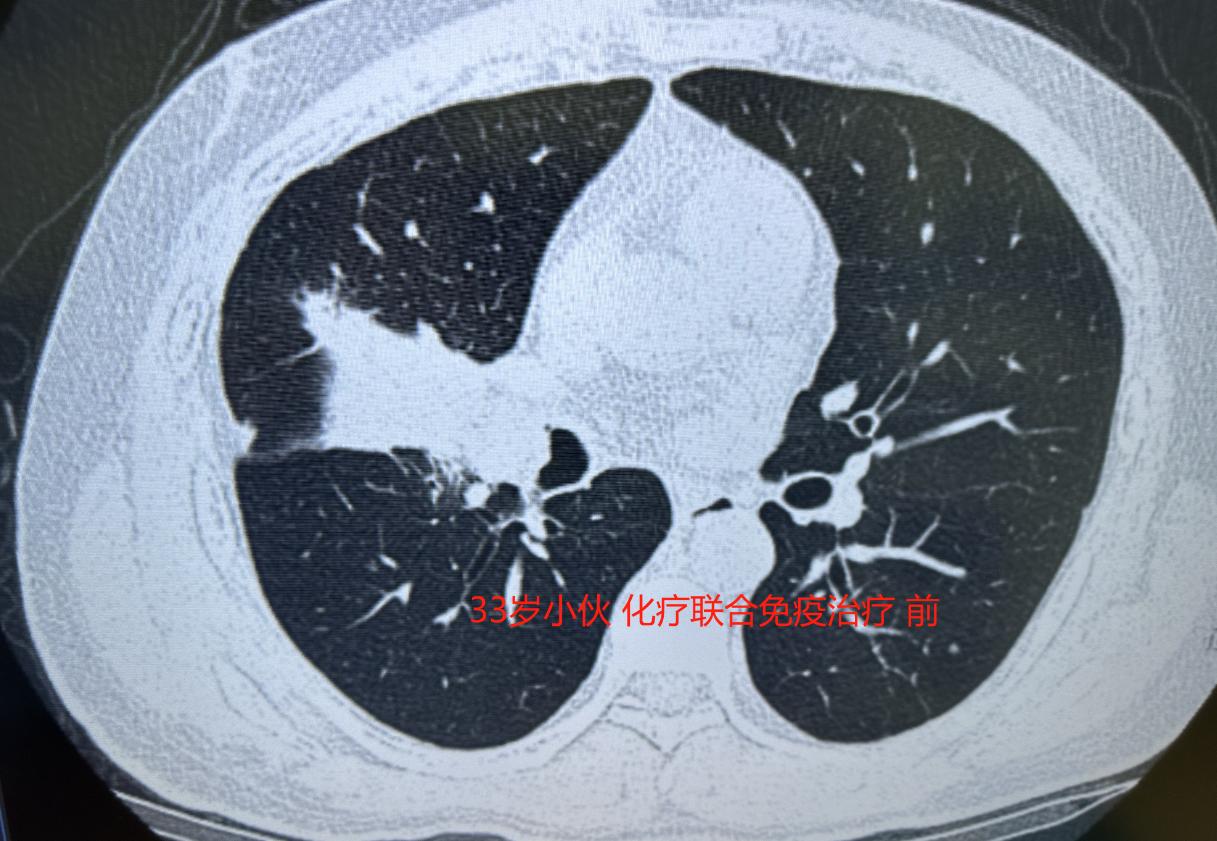

33岁的年轻人,因为咳嗽得厉害去检查,发现右肺中叶长了一个很大的肿瘤,进一步检查确诊肺癌,幸好还没有转移到其他地方,但整个右肺中叶几乎被肿瘤占满,周围的血管和气管也都受到了侵犯。

按照常规,像他这样没有基因突变的肺癌患者,目前效果比较好的方案是先做“化疗联合免疫治疗”,等肿瘤缩小后再手术,这样切除得更彻底。有效率本来有百分之七八十,算是比较高的。

但没想到,三次治疗下来,肿瘤一点都没缩小——这个方案对他竟然没起作用。